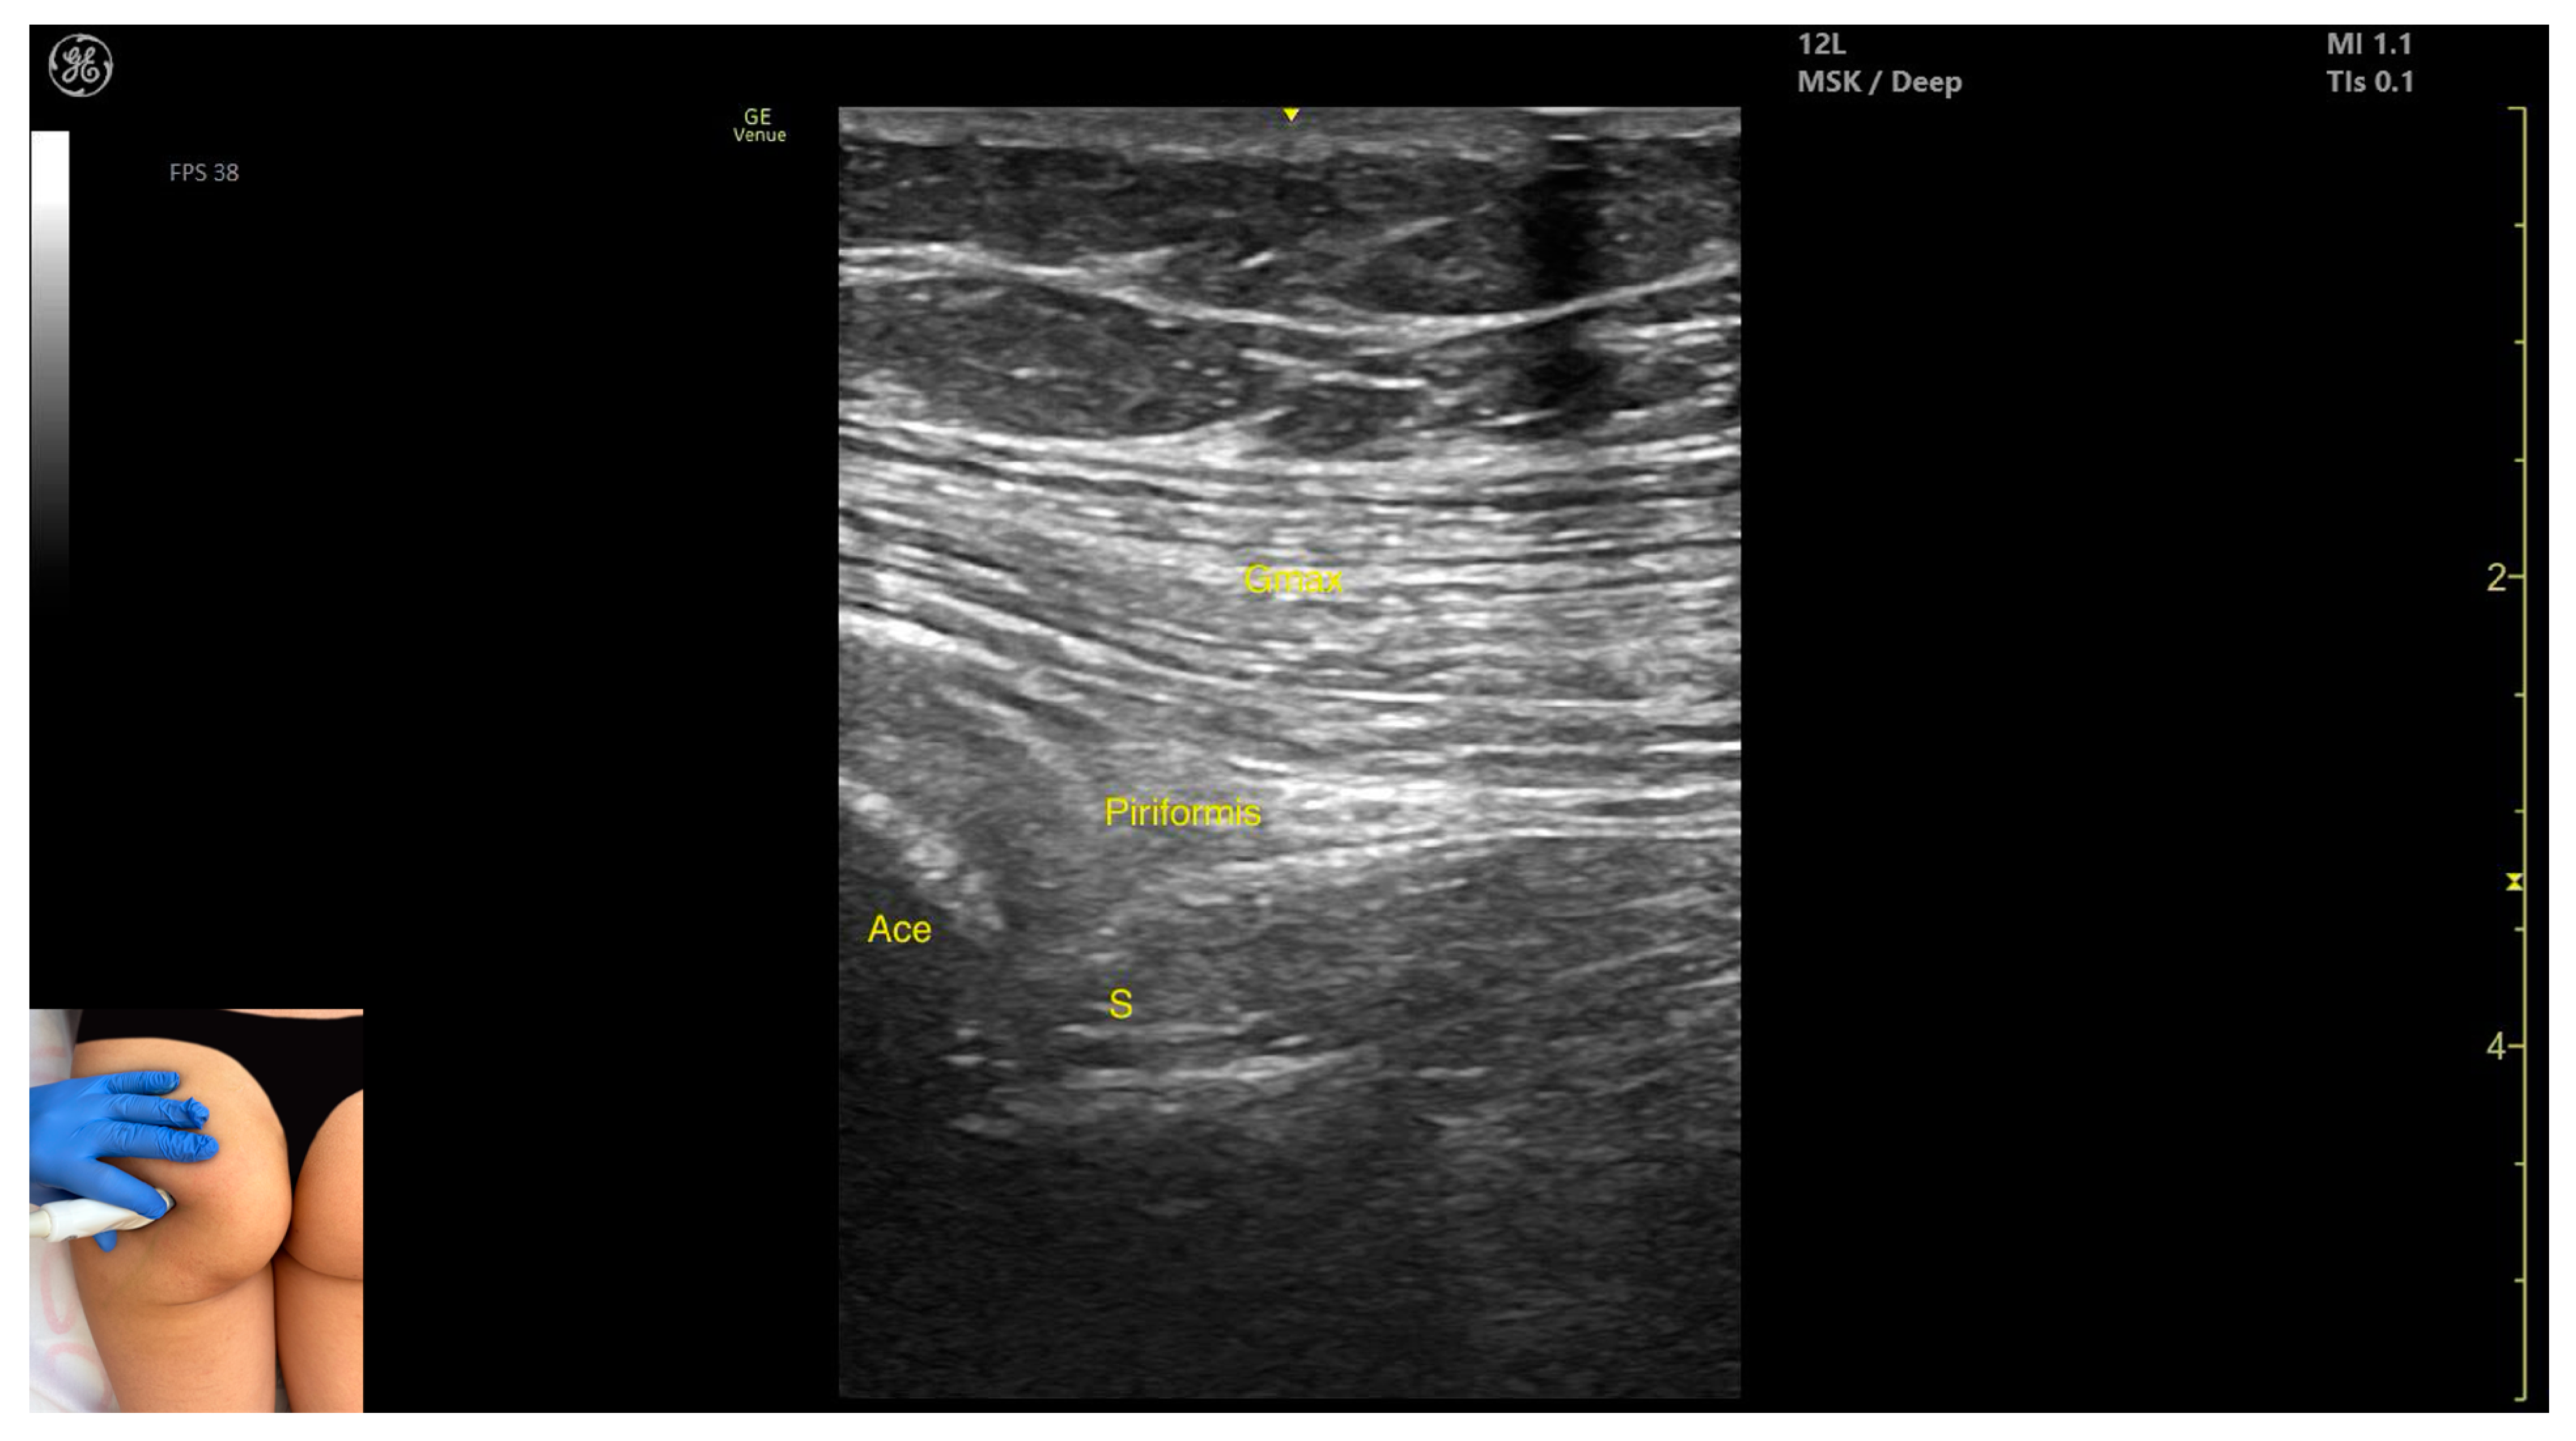

3.2. Piriformis

3.2.2. Ultrasound Identification

3.2.3. Key Ultrasound Landmarks

- Muscle morphology: It is part of the deep gluteal muscle group, along with the obturator internus, obturatorus externus, superior gemellus, inferior gemellus, and quadratus femoris.

- Muscle position: At this level, it appears as the first muscle mass superficial to the acetabular cortex. The sciatic nerve lies in close proximity, located deep to the piriformis.

- External fascia: It presents a well-defined fascia separating it from the gluteus maximus, which is important during botulinum toxin injection.

- Dynamic evaluation: During dynamic evaluation, scanning 2–3 cm distally toward the ischial tuberosity, the piriformis muscle tapers and disappears, and the obturator internus muscle becomes visible. Superficial to the obturator internus, the gluteus maximus and the sciatic nerve (within the intermuscular fascia) can be observed. Muscle contraction is visible during the external rotation and abduction of the femur at the hip joint.